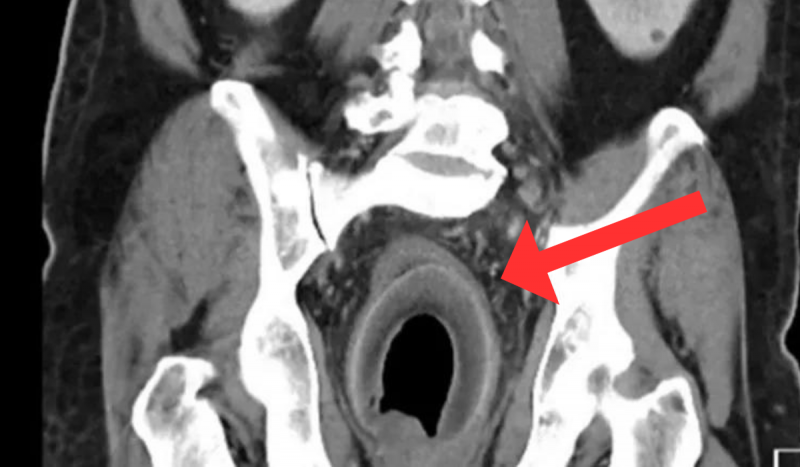

Exame de imagem mostrando coco no ânus de pacientePaciente enfiou fruta no ânus em busca de prazer e corpo estranho apareceu em exames de imagem – Foto: Daily Star/Reprodução/ND

O homem de 56 anos teve dores intensas e constipação severa por não conseguir retirar o item de dentro da cavidade anal. A fruta chegou a ficar dentro do paciente por dois dias e foi introduzida no orifício para estimulação sexual durante a masturbação.

Após as tentativas frustradas do paciente de remover o coco, os médicos optaram pela laparotomia exploratória – procedimento feito a partir de uma incisão no abdômen – que conseguiu tirar a fruta que media 7,5cm por 5,7cm.